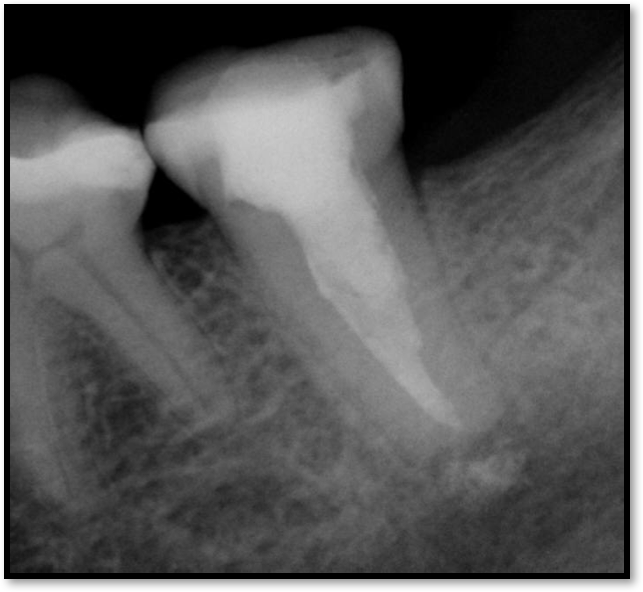

If a tooth stands alone, greater forces will be placed on it because it has no adjacent teeth to provide support. This situation will affect the decision-making process for placing a post. Figure 3 shows a tooth that was on an island and would be having three implants placed in front of it. The tooth would take a much greater beating than another tooth that had support proximally. Even though it had a good root canal, the clinician would need to account for whether the tooth would last until the implants integrated. Figure 4 shows a case that would quickly proceed to implants. The patient had a less-than-ideal bridge for over a decade, with decent endodontics and functionality. There was also an overhang on the premolar. The post was not ideal in this case because there was one distal canal and not all the gutta-percha was removed from it. An intimate fit should be the goal with the post and the walls. Whether using a threaded or non-threaded post, there should not be excess gutta-percha because it is not as solid as the tooth and will lead to greater movement. That movement on the tooth and bridge will create too much force and result in demise.

Fig 4. Case that quickly would proceed to implants.

Figure 4